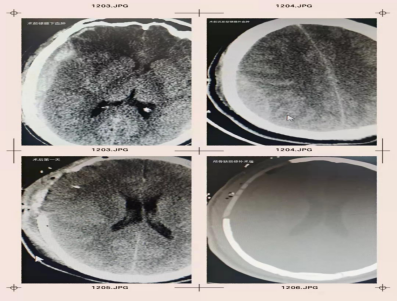

該患者男性,22歲,車禍外傷后昏迷約1小時由急診收入院。經顱腦CT檢查,右側額顳頂硬膜下血腫,右額顳葉多發(fā)挫裂傷;左頂枕骨骨折。查體后發(fā)現(xiàn)深昏迷,GCS評分7分,雙眼瞳孔等大等圓,直徑約3.0mm,對光反射及調節(jié)反射遲鈍,疼痛刺激肢體可躲避。入院診斷為急性重型顱腦損傷,神經外科孟凡興主任醫(yī)師根據患者顱腦CT及查體表現(xiàn),建議患者做開顱血腫清除手術。孟凡興主任與患者家屬解釋病情及治療建議后,家屬簽字同意手術治療方案。

術前,孟凡興主任醫(yī)師查閱患者顱腦CT,考慮患者受傷時間為1個小時,不排除遲發(fā)型顱腦損傷,常規(guī)去手術室行開顱手術前需再次復查顱腦CT。為進一步緩解顱腦壓力,為開顱血腫清除手術爭取有利時間,完善消毒后于床旁行右側硬膜下血腫穿刺引流術,穿刺成功后,黑色不凝血流入無菌引流袋,暫時緩解了顱腦壓力。穿刺術后立即復查顱腦CT,CT結果顯示右側硬膜下血腫較前減少,穿刺針在位,遲發(fā)型右側頂部硬膜外血腫。

術后,經顱腦CT復查顯示,患者顱內血腫基本清除。手術的順利與成功,離不開臨沂市第三人民醫(yī)院急診綠色通道、神經外科及重癥科室人員有條不紊的急救治療流程,更離不開患者及家屬的信任和配合。